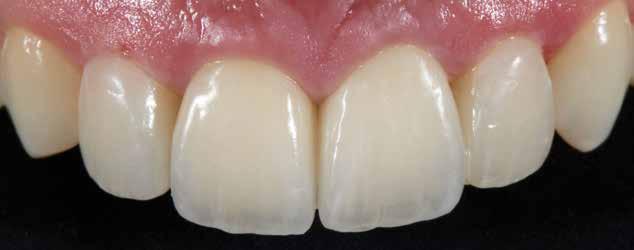

Az általunk alkalmazott adhezív rendszerek hatékonyságát nagymértékben növelhetjük azáltal, hogy a fogakat minimál invazív módon, azaz csak zománcon belül preparáljuk, és a kerámia héjakat kofferdám izolálásban ragasztjuk. Jelen esetismertetésünknek az volt a célja, hogy bemutassuk, hogyan lehet az adekvát módon kivitelezett kofferdám izolálással megelőzni

a munkaterület nyállal, vérrel vagy szulkusz-váladékkal történő kontaminációját. A megfelelő méretben kialakított perforációs nyílások és köztük lévő optimális távolság elengedhetetlen ahhoz, hogy a kofferdámot ideális módon tudjuk felhelyezni. Ezzel az esettel azt is bizonyítjuk, hogy a gumilepedő levegőfújással, fogselyemmel és teflonszalagok segítségével történő beforgatásával az ínyvérzés kialakulását el lehet kerülni. Ismételten szeretnénk hangsúlyozni, hogy a megfelelő kofferdám kapcsok használata nélkül nem tudtuk volna a preparált csonkszélt a gumilepedő szélétől eltartani. A kezelés során elért eredményeket jól alátámasztotta, hogy a páciens az ötéves kontroll vizsgálat során teljesen elégedett volt.

8. ábra. Az ultravékony héjak adhezív módszerekkel történő ragasztása. (A): Az elkészült héjak. (B): A fogfelszínek kofferdám izolálásban történő foszforsavas kondicionálása. (C): Az adhezív felvitele. (D): A héjak fényre kötő rezin alapú ragasztócementtel történő ragasztása.

ás, majd #0-ás retrakciós fonalakat (Ultrapak, Ultradent Products Inc, South Jordan, Utah, Egyesült Államok) helyeztünk. A végső precíziós lenyomatot polivinil-sziloxán lenyomatanyaggal (Virtual 380, Ivoclar Vivadent AG, Schaan, Liechtenstein) vettük. A fogtechnikai fázisban ultravékony (0,5 mm-nél vékonyabb) földpátkerámia héjak elkészítését kértük (Super Porcelain Ex-3, Kuraray Noritake Dental, Tokió, Japán), (7. ábra). A kerámia héjak készre vitelét követően a próba során a héjakat a helyükre illesztettük a széli zárást, az így kialakított fogformák ellenőrzése céljából. A páciens elégedett volt az így kapott látvánnyal. A végleges ragasztás kofferdám izolálásban történt. A preparált fogak felületét először 37%-os foszforsavval (Total Etch, Ivoclar Vivadent) 15 másodpercen keresztül kondicionáltuk, majd vízzel leöblítettük (8. ábra). A kondicionált zománcfelszíneket Adhese Universal (Ivoclar Vivadent) adhezívvel kezeltük. A kerámiahéjak homorú felszíneit 5%-os folysavval (IPS Ceramic Etching Gel, Ivoclar Vivadent) 20 másodpercen át kondicionáltuk, majd a felszíneket Monobond Plus primerrel (Ivoclar Vivadent) vontuk be (7. és 8. ábrák). A héjakat fényre kötő rezinalapú ragasztócement (Variolink Esthetic LC, Ivoclar Vivadent) applikálását követően a helyükre illesztettük. A kifolyó cementfelesleg eltávolítását követően minden felszínt (labiális, palatinális, meziális és distális) LED-es polimerizációs lámpával (VALO Cordless, Ultradent) 40 másodpercen keresztül megvilágítottuk.